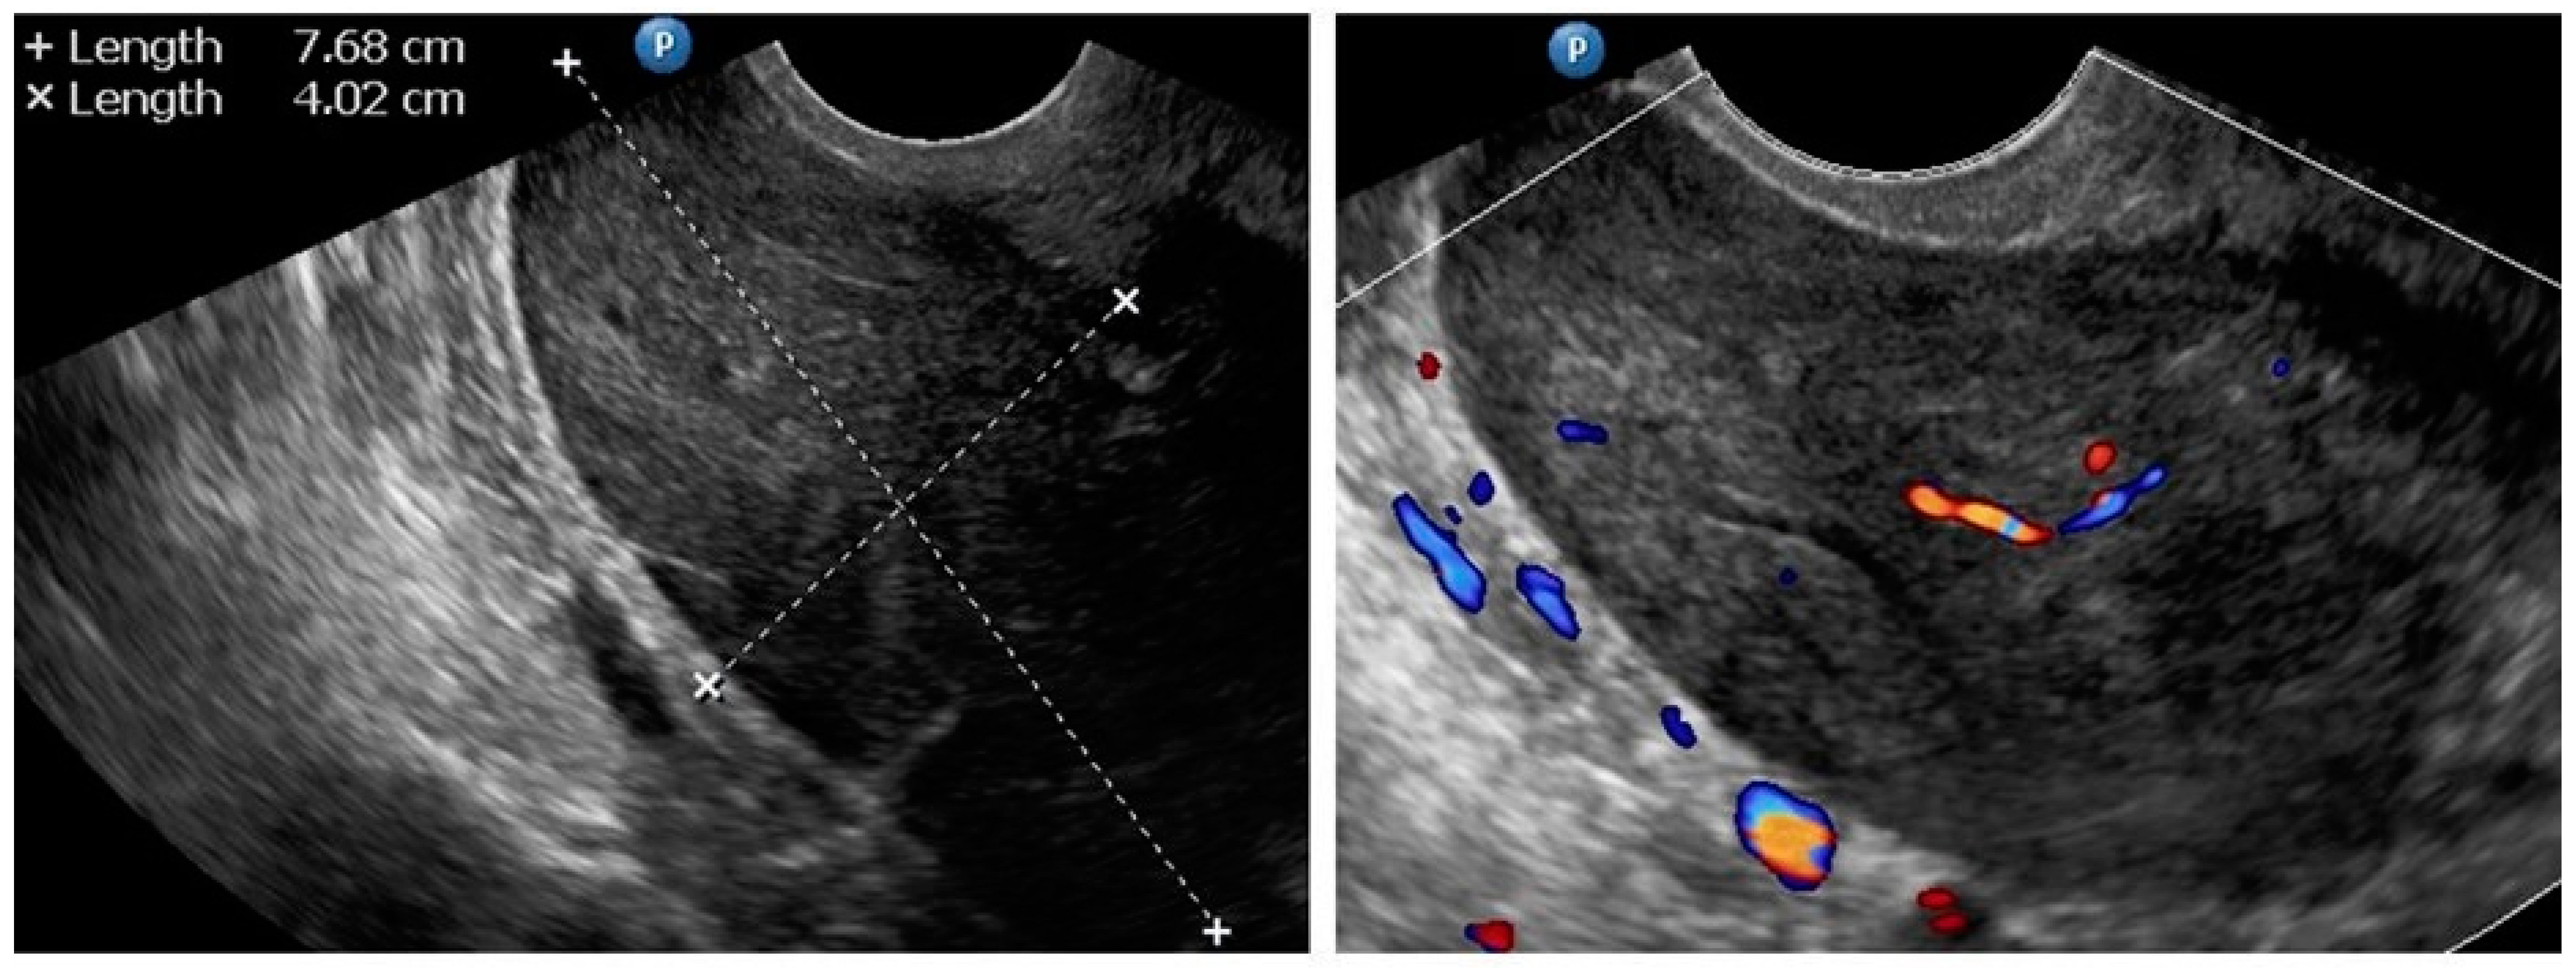

| 6 (38) | Atypical uterine lesion | Figure A6 | Yes | No | Leiomyoma, epithelioid variant (UG-TUC core needle biopsy) | Yes (lesion enlarged during follow-up) | Leiomyoma, epithelioid variant | Yes | Yes |